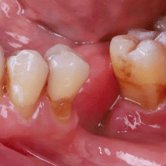

Pérdida de múltiples dientes

La pérdida de múltiples dientes es la ausencia de varios dientes que puede ser resultado de caries, enfermedades periodontales o traumatismos.

Los pacientes notan varios espacios vacíos en su boca, lo que afecta su capacidad para masticar y hablar adecuadamente.

El tratamiento incluye la colocación de varios implantes dentales para restaurar la función y la estética.